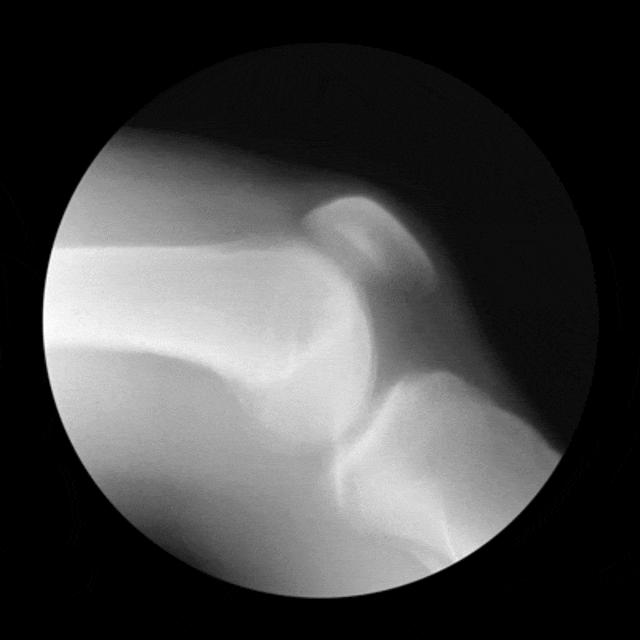

但很少有人知道,膝关节由股骨、髌骨、胫骨、韧带、半月板、滑膜等多个结构组成,疼痛可能是上面任何一个部位受伤造成的。

膝关节软骨损伤分为两大类:慢性磨损退变以及急性外伤导致的软骨剥落。

慢性软骨磨损退变往往是由髌骨关节、股骨髁软骨磨损引起的,是骨关节炎的早期表现。